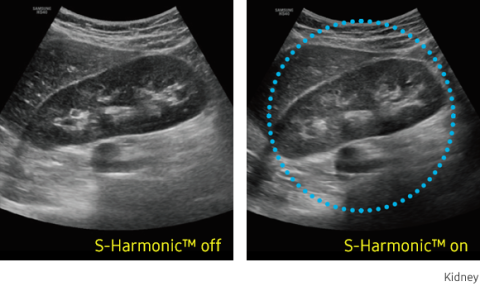

S-Harmonic™ reduces signal noise and provides more uniform ultrasound images by improving near to far image clarity.